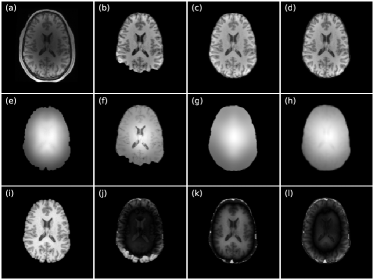

Table 2 shows the quantitative results of FSL, FS and NPP(see visualization results in Supplementary S1). NPP outperforms the baselines on all metrics. From Table 2, we see that FreeSurfer’s reconstruction is better than BET’s, but the bias field estimates are relatively worse. We can appreciate this in the figure in Supplementary S1, as we observe that FS’s bias field estimate (f) contains too much high-frequency anatomical detail.

Figure 6: Representative slices of intensity normalization performance on HCP T1w brain images. (a) input image; (b-d) intensity normalized outputs from FreeSurfer, FSL, and NPP with λ=0.1𝜆0.1\lambda=0.1; (e) ground truth bias field; (f-h) bias fields estimated by the corresponding methods; (i) ground-truth intensity normalized image; (j-l) prediction error maps corresponding to (b-d).